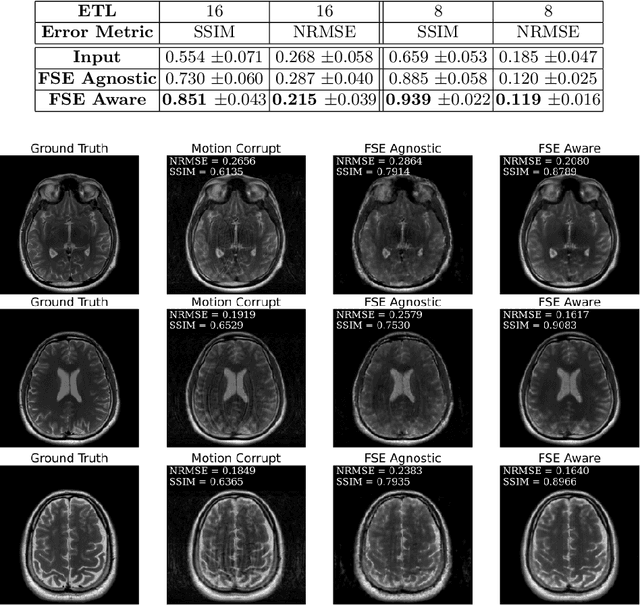

Abstract:Magnetic Resonance Imaging (MRI) is a widely used medical imaging modality boasting great soft tissue contrast without ionizing radiation, but unfortunately suffers from long acquisition times. Long scan times can lead to motion artifacts, for example due to bulk patient motion such as head movement and periodic motion produced by the heart or lungs. Motion artifacts can degrade image quality and in some cases render the scans nondiagnostic. To combat this problem, prospective and retrospective motion correction techniques have been introduced. More recently, data driven methods using deep neural networks have been proposed. As a large number of publicly available MRI datasets are based on Fast Spin Echo (FSE) sequences, methods that use them for training should incorporate the correct FSE acquisition dynamics. Unfortunately, when simulating training data, many approaches fail to generate accurate motion-corrupt images by neglecting the effects of the temporal ordering of the k-space lines as well as neglecting the signal decay throughout the FSE echo train. In this work, we highlight this consequence and demonstrate a training method which correctly simulates the data acquisition process of FSE sequences with higher fidelity by including sample ordering and signal decay dynamics. Through numerical experiments, we show that accounting for the FSE acquisition leads to better motion correction performance during inference.